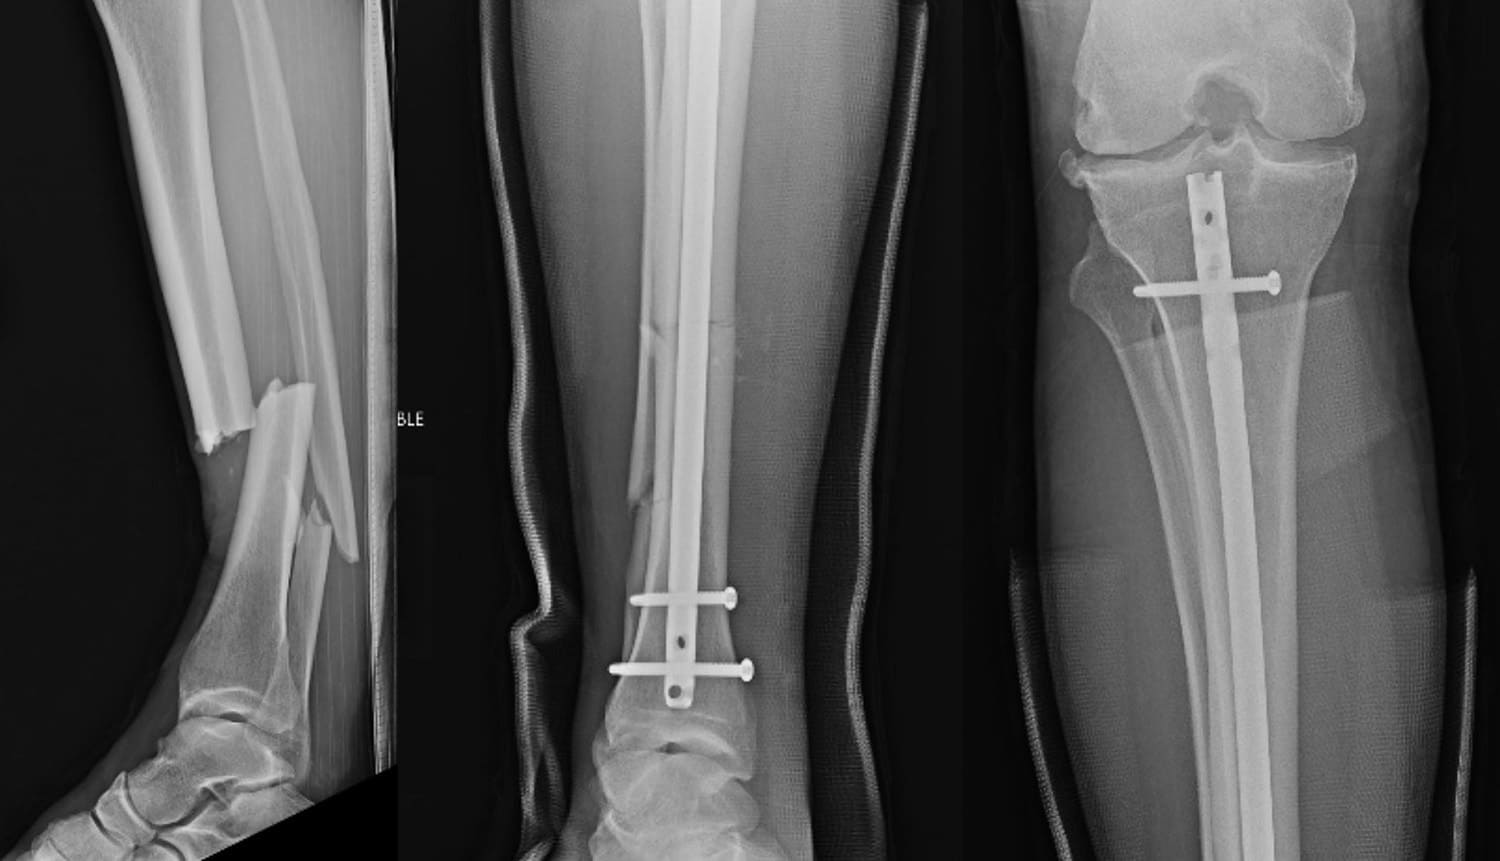

Также боец UFC поделился рентгеновскими снимками голени до и после проведения операции. Они дают в полной мере понять, какими серьезными были повреждения Криса:

Рентгеновские снимки до и после пережитого вчера кошмара. Сейчас нас больше всего волнует кость, проткнувшая мою икру и кожу на ноге. Необходимо убедиться, что рана не заражена”.

Перелом Криса Вайдмэна